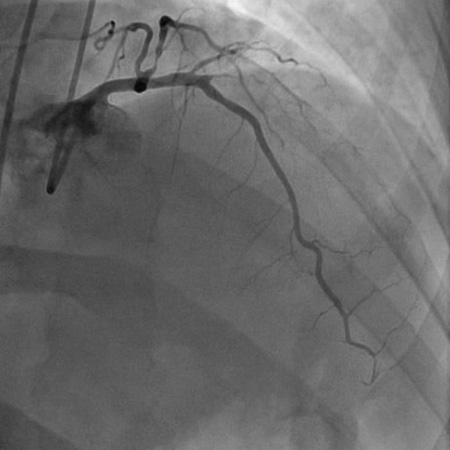

Invasive angiography is not typically used for initial diagnosis of chronic coronary disease, although in patients with a high pre-test probability it may be used for confirmation of the diagnosis, risk stratification, and to identify appropriate candidates for revascularisation. It may also be used for diagnosis when initial non-invasive testing is inconclusive.[24][Figure caption and citation for the preceding image starts]: Angiogram (right anterior oblique caudal projection) in a 55-year-old man with a 1-month history of angina on exertion. A 90% proximal stenosis of obtuse marginal 1 is present, explaining the patient's lateral ischaemiaFrom the collection of Dr S.D. Fihn; used with permission [Citation ends].